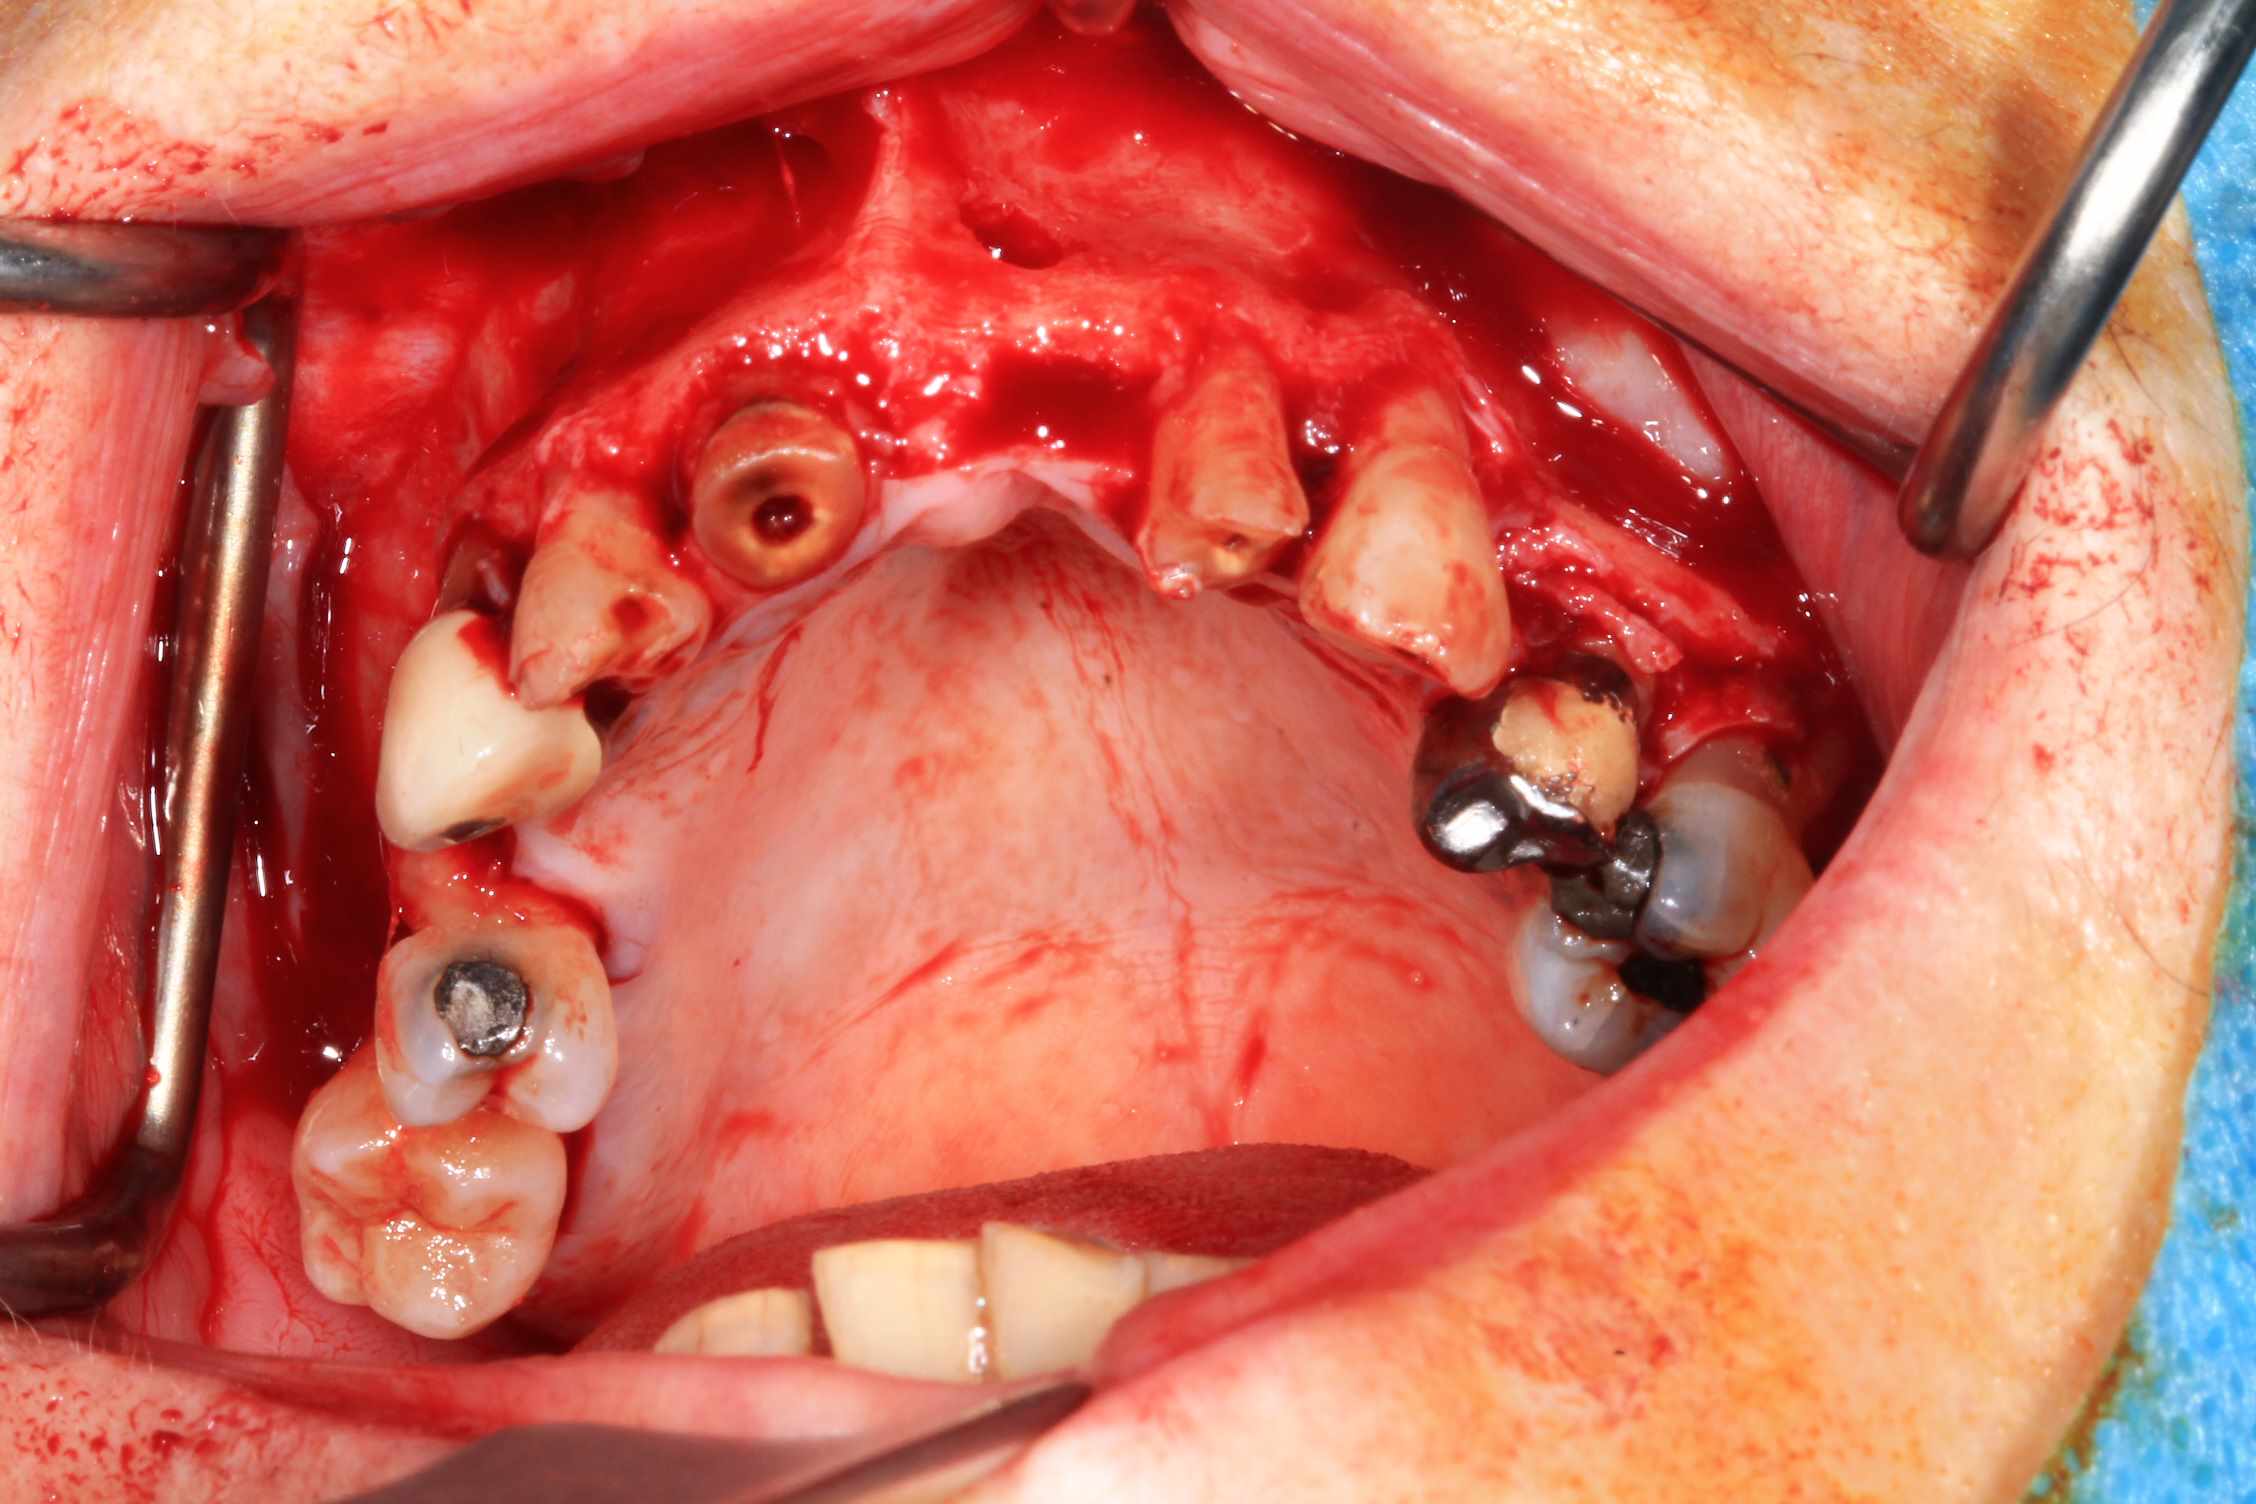

Cas 5 : extraction et all on 4. en bas , pas du tout d'os : décision de bridge complet avec une extension de chaque coté.

Modélisation : labo lio. Design et impression du guide : Teeth projet. Bridge full zircone katana myio rosenscrew en mise en charge instantanée , labo LIO.

Guide a etage avec fixtion de l'etage clavette par rapport aux dents avant extraction. Extraction.

Fixation du guide de forage sur le guide clavette. pose des implants, des piliers ( tres classique ), et du bridge zircone rosenscrew. Stickybone The Graft, sutures suspendues et résultat post op et un mois.